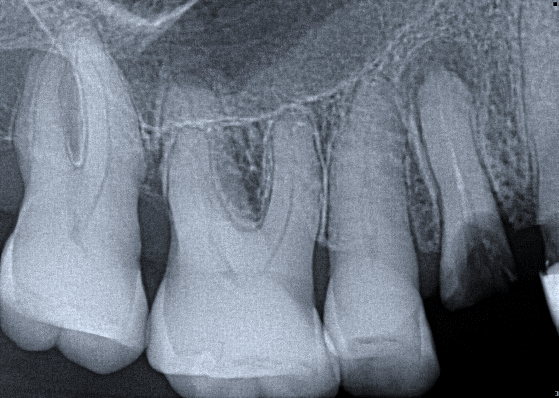

3. (Select ONE OR MORE correct answers)

Which of the following may complicate the extraction of tooth 4.7?